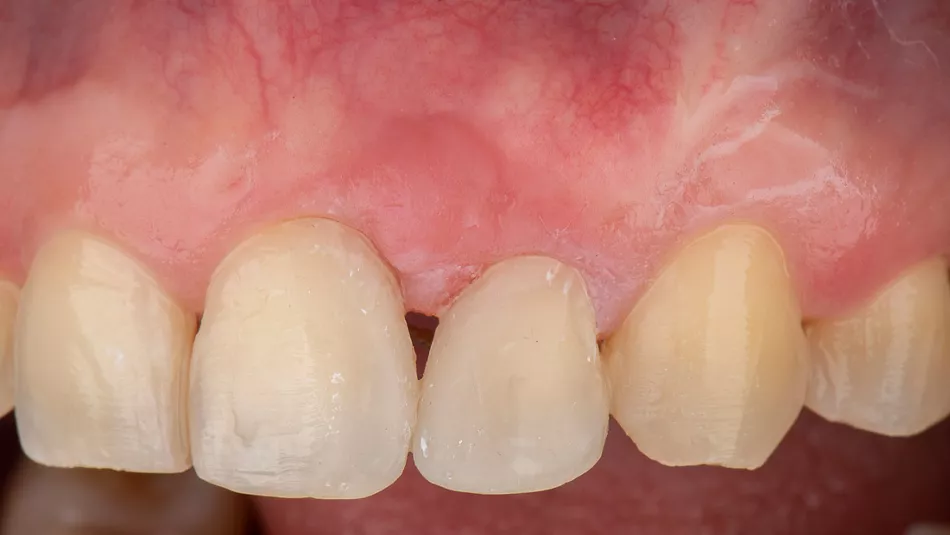

Control at one year after the second surgery. The diastema between incisors was closed with controlled movements (Fig. 14). The radiographic control revealed an important interdental bone fill and periodontal stabilization of teeth #21 and #22 (Fig. 15).

Treatment outcomes

Clinical outcomes exceeded patients’ expectations and were very satisfactory for the ortho-perio team. The soft tissues remain stable after 5 years of interdisciplinary treatment (Fig. 16). The patient expressed deep gratitude for saving his teeth: “Thanks to the entire team for collaborating so diligently over these years; the wait was truly worthwhile.”

Fig. 16